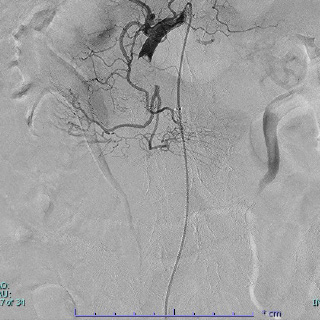

例えば腸管に血液を供給する上腸間膜動脈という血管が血液の塊(血栓)や狭窄によって閉塞し、腸管が壊死する病気があります。このような病気では、壊死した腸管が多くなると、たとえ手術で壊死した腸管を切除しても長期間生存することはできません。当科では術中もしくは術前に放射線科と協力し動脈の中にある血栓を回収したり、血管の狭い部分を広げたりする事で壊死する腸管を少なくする治療を行っています。

術中血栓吸引療法